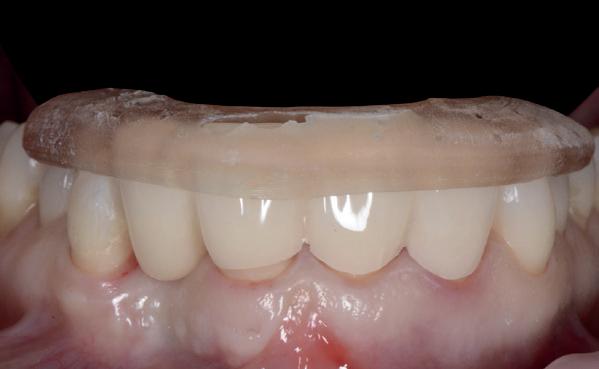

1a. Verlies van buccaal bot na immediaat plaatsing 1b. Jumping Gap 1c-j. Guided geplaatst met een tijdelijke kroon indirect vervaardigd

Om alle bovenstaande redenen plaats ik momenteel, bij voorkeur, geen implantaten meer immediaat. Natuurlijk zijn er wel uitzonderingen. Maar die zijn jaarlijks inmiddels op één hand te tellen. Dat betreft alleen frontelementen met tenminste 2 mm autoloog bot buccaal (minder dan 0.5 % van de casussen volgens Kan et al.). Uiteraard dan guided geplaatst met een tijdelijke kroon indirect vervaardigd (afbeelding 1c-1j).